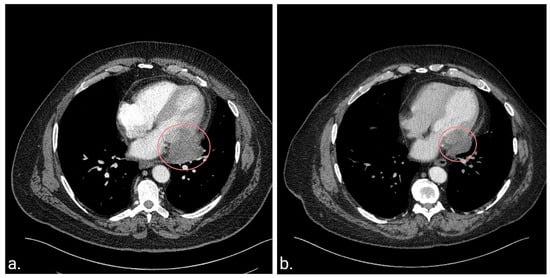

At the age of 62 years, while evaluating his lymphedema symptoms, abdominal and pelvic computed tomography scans (CT) revealed a pericardial mass. The patient did not experience any symptoms attributed to the cardiac mass at the time of diagnosis. Subsequent chest CT (Figure 1a) and cardiac magnetic resonance imaging (MRI) revealed a solitary 5.2 × 4.7 × 3.5 cm mass involving the pericardium and infiltrating the lateral wall of the left ventricle. Cardiac MRI was selected to complement the CT findings due to its superiority in characterizing soft tissue and its high specificity in distinguishing between benign pseudomasses and malignant cardiac tumors [60,61]. Additionally, MRI becomes particularly relevant when recurrent soft-tissue sarcoma is suspected due to its high diagnostic accuracy [62].

Figure 1.

Chest computerized tomography (CT) scans at diagnosis of the cardiac metastasis and 10 years post-treatment. (a). CT scan before the initiation of chemotherapy and radiotherapy demonstrating a heterogeneous mass located in the pericardium and extending into the left ventricle. (b). The latest CT scan 10.5 years after diagnosis demonstrating a residual soft tissue mass centered in the left posterolateral pericardium, which has remained stable since the completion of therapy.

CT scan 8 weeks after chemotherapy discontinuation showed a slight increase in tumor size, but subsequent imaging 6 weeks later revealed tumor stability. Surgical resection was deemed high-risk, and as the patient had stable disease with a low likelihood of available chemotherapeutic modalities further reducing the size of the mass, observation was recommended. Surveillance included CT chest, abdomen, and pelvis every 2–3 months for 1.5 years, every 6 months until 5 years, then annually. The patient’s disease has remained stable to date for >10 years since the completion of therapy (Figure 1b). Notably, previous treatment was well-tolerated in terms of cardiac toxicity, with the patient showing no signs or symptoms of declining cardiac function, and a cardiac MRI performed five years post-treatment revealed only mild hypokinesis of the basal lateral left ventricular wall, with a preserved left ventricular ejection fraction of 57%.